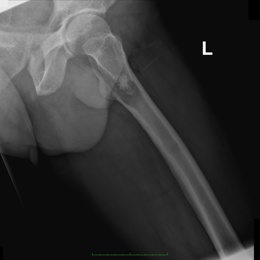

Radiographic imaging is used to help form a diagnosis. These include X-Ray, MRI, CT and Bone Scans

An example of a dedifferentiated chondrosarcoma X-Ray is shown.

15B) Dedifferentiated Chondrosarcoma Left Femur XR Lateral T HIP FROG Left